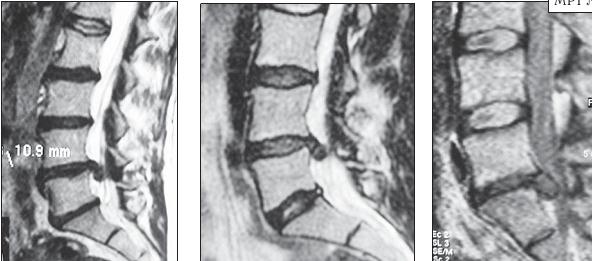

На серии снимков МРТ № 25 наблюдаются дорсальные грыжи межпозвонковых дисков в поясничном отделе позвоночника в сегментах LIV-LV Lv—SI Такие комбинации, в которых образуются по нескольку грыж, межпозвонковых дисков одновременно, случаются довольно часто на более поздних стадиях развития дегенеративно-дистрофического процесса. В общем, беда не приходит одна, «несчастье» любит, компанию МРТ № 26